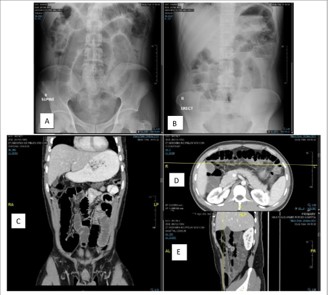

CT reported a markedly distended stomach and small bowel with no clear area of transition zone that could be seen; multiple enlarged mesenteric lymph nodes and engorgement of mesenteric vessels are noted, mainly at the mid and left abdomen (Figure 1).

Figure 1: Radiology finding Abdominal X-ray and CT. (A,B) Abdomen x-ray showed air-fluid level. (C,D,E) CT abdomen showing small bowel complete obstruction with transitional zone seen distal ileal loops.